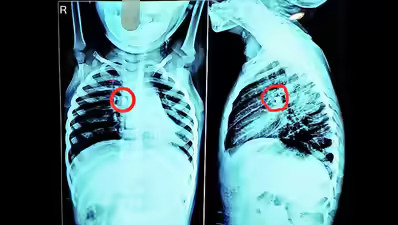

Stone removed from toddler’s windpipe